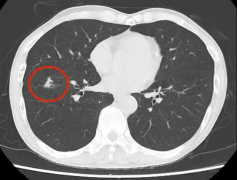

胸部CT常见的影像表现及对应的诊断要点环医疗1

为何孩子常说肚子疼?该怎么办?环医疗3- 环医疗胸部CT常见的影像表现及对应的诊断要点